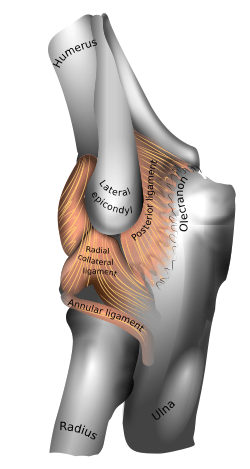

Ligaments

Left: anterior and ulnar collateral ligaments

Right: posterior and radial collateral ligaments

The elbow, like other joints, has ligaments on either side. These are triangular bands which blend with the joint capsule. They are positioned so that they always lie across the transverse joint axis and are, therefore, always relatively tense and impose strict limitations on abduction, adduction, and axial rotation at the elbow.[7]

The ulnar collateral ligament has its apex on the medial epicondyle. Its anterior band stretches from the anterior side of the medial epicondyle to the medial edge of the coronoid process, while the posterior band stretches from posterior side of the medial epicondyle to the medial side of the olecranon. These two bands are separated by a thinner intermediate part and their distal attachments are united by a transverse band below which the synovial membrane protrudes during joint movements. The anterior band is closely associated with the tendon of the superficial flexor muscles of the forearm, even being the origin of flexor digitorum superficialis. The ulnar nerve crosses the intermediate part as it enters the forearm.[7]

The radial collateral ligament is attached to the lateral epicondyle below the common extensor tendon. Less distinct than the ulnar collateral ligament, this ligament blends with the annular ligament of the radius and its margins are attached near the radial notch of the ulna.[7]